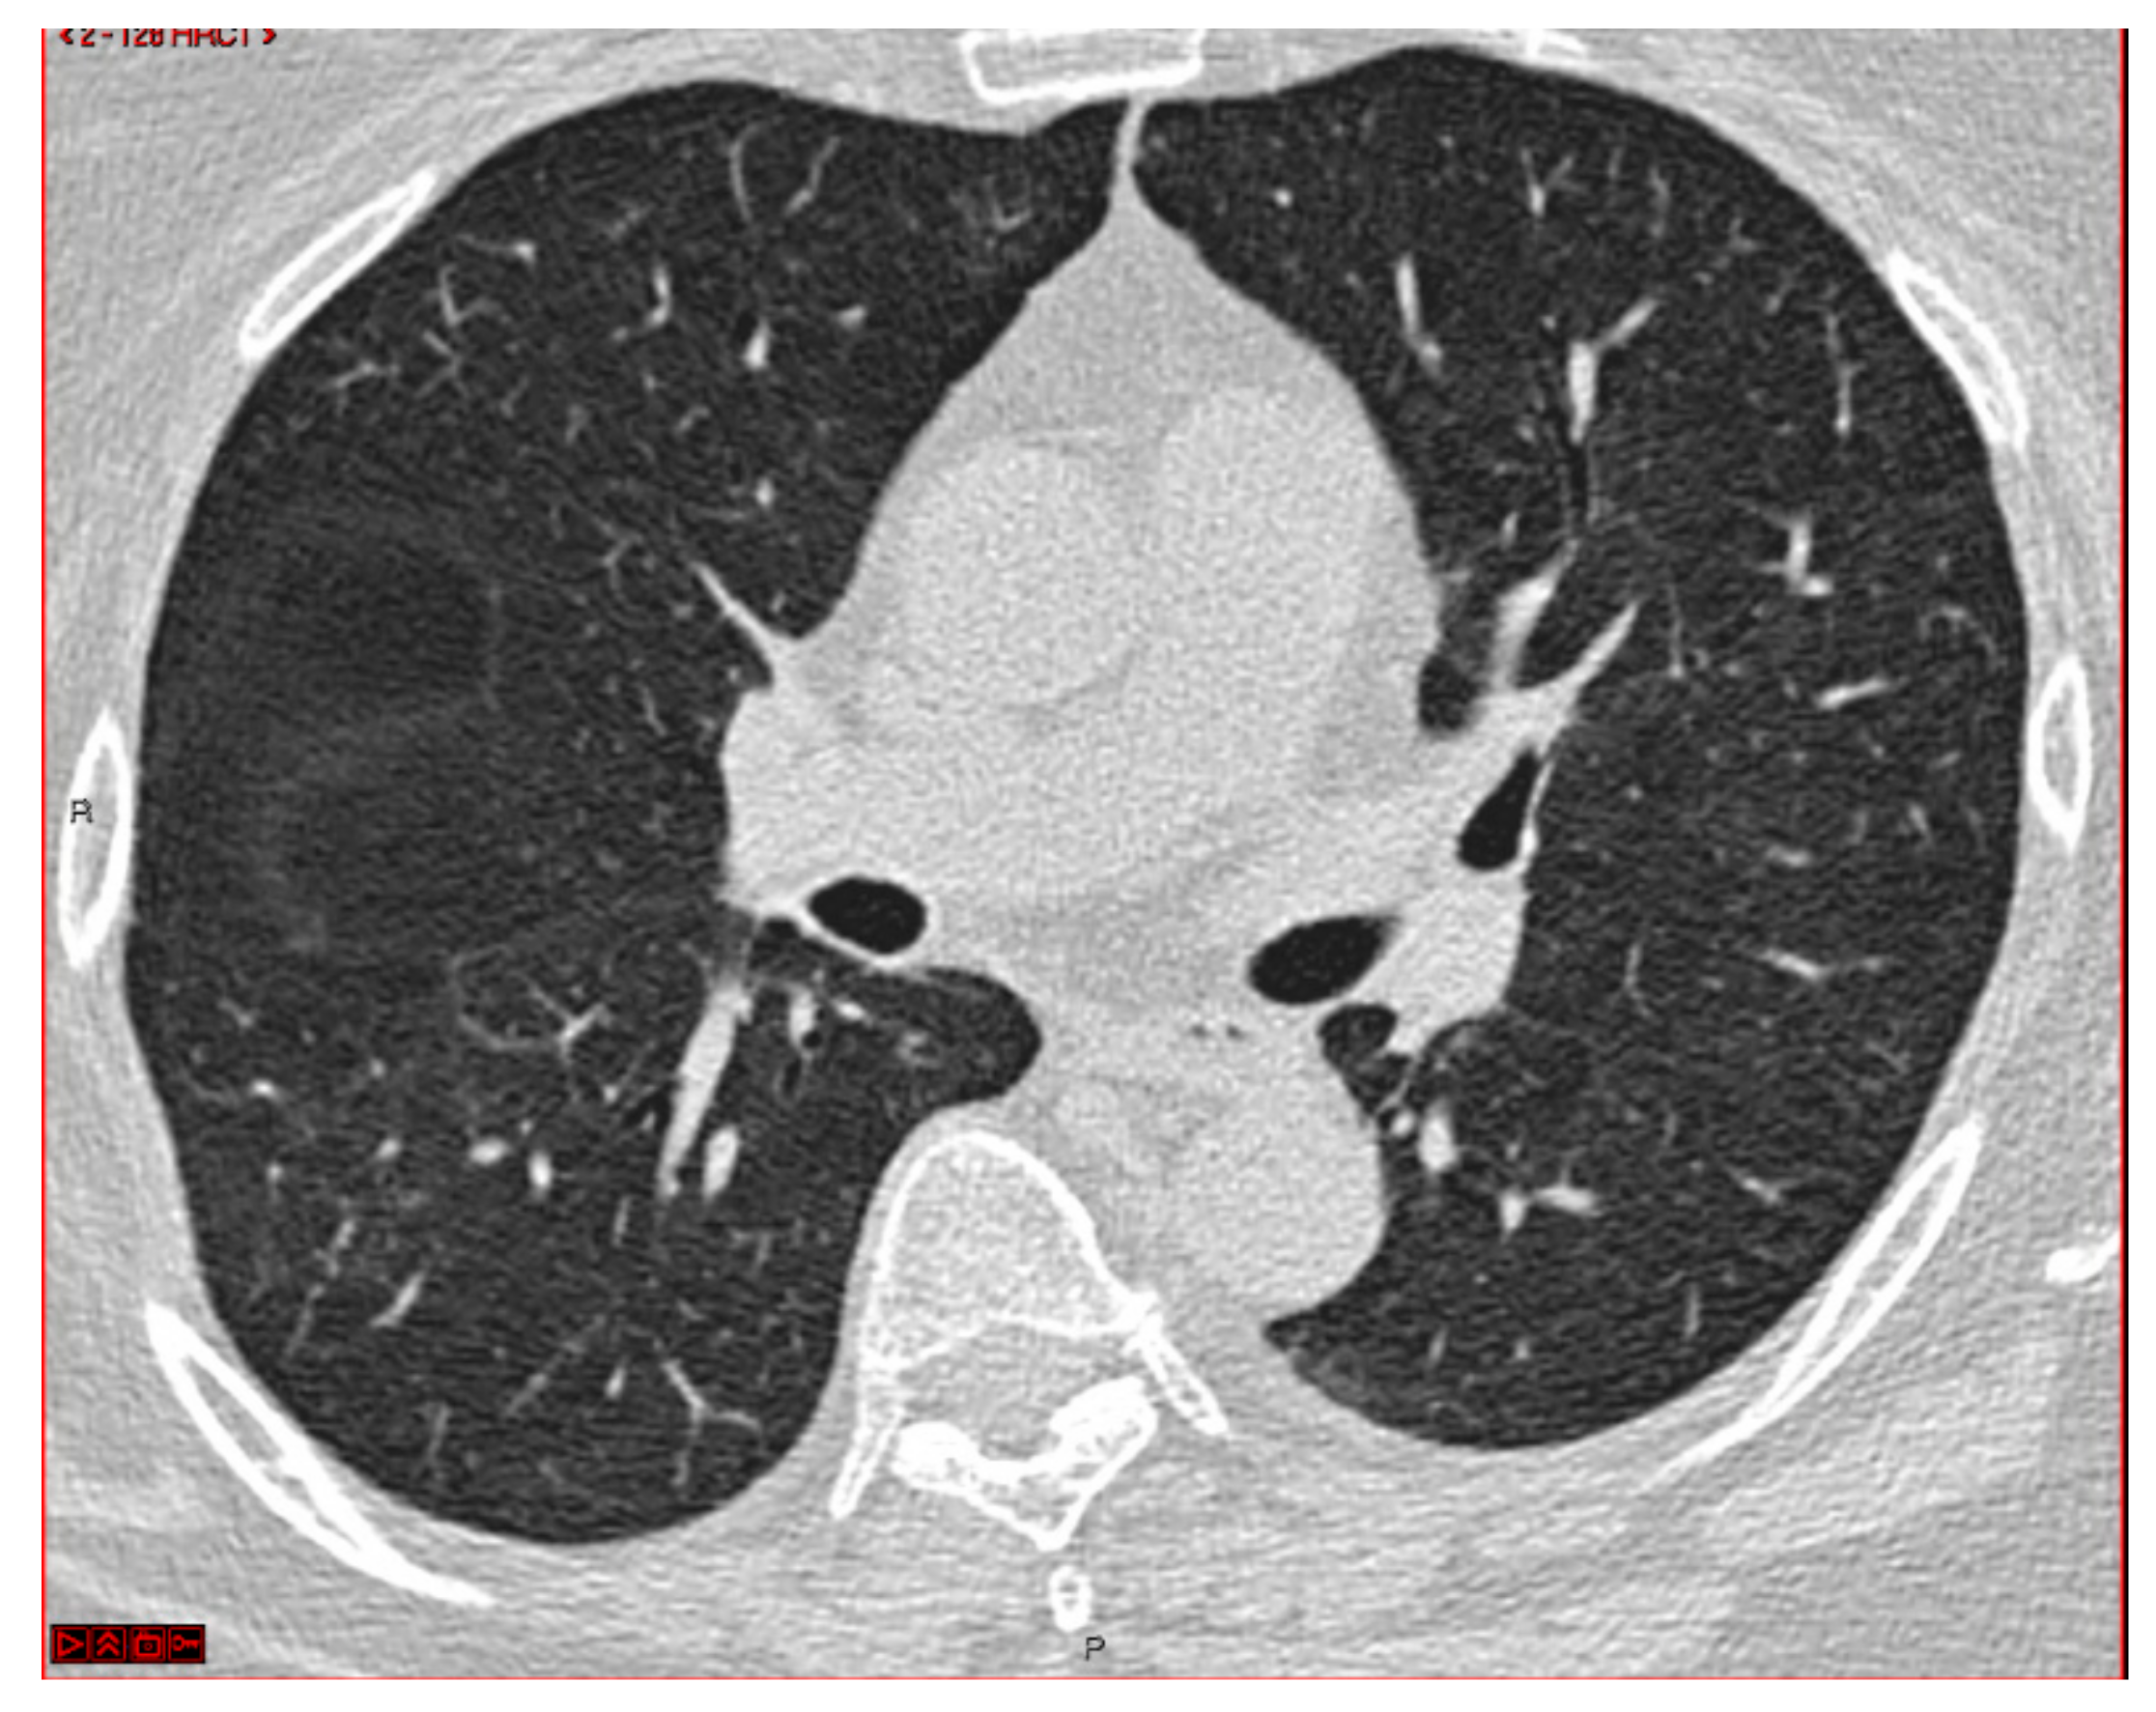

Diagnosis of Organizing Pneumonia with an Ultrathin Bronchoscope and Cone-Beam CT: A Case Report

2. Case Presentation